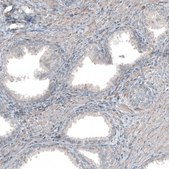

All Prestige Antibodies Powered by Atlas Antibodies are developed and validated by the Human Protein Atlas (HPA) project and as a result, are supported by the most extensive characterization in the industry.

The Human Protein Atlas project can be subdivided into three efforts: Human Tissue Atlas, Cancer Atlas, and Human Cell Atlas. The antibodies that have been generated in support of the Tissue and Cancer Atlas projects have been tested by immunohistochemistry against hundreds of normal and disease tissues and through the recent efforts of the Human Cell Atlas project, many have been characterized by immunofluorescence to map the human proteome not only at the tissue level but now at the subcellular level. These images and the collection of this vast data set can be viewed on the Human Protein Atlas (HPA) site by clicking on the Image Gallery link. We also provide Prestige Antibodies® protocols and other useful information.

• IHC tissue array of 44 normal human tissues and 20 of the most common cancer type tissues.